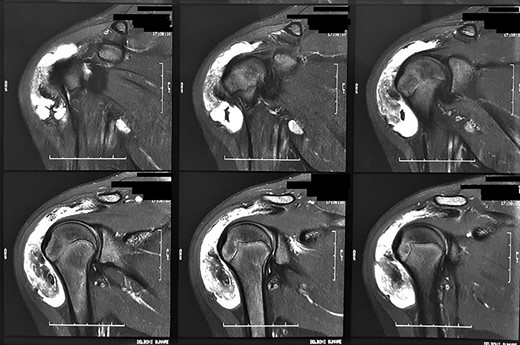

Magnetic resonance images of the patient. We observed coronal sections of the right shoulder in a sensitive liquid sequence, showing intense diffuse subacromial synovial thickening, associated with grouped images in the topography of the bursa.

Radiographs were requested, which did not demonstrate any significant findings. For better diagnostic clarification, a nuclear magnetic resonance imaging of the right shoulder was requested, which showed diffuse synovial thickening and abundant bursal fluid distension without intra-articular involvement (Fig. 2).